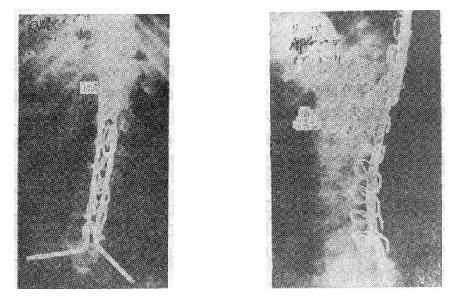

(六)胸10以上的高位胸椎骨折截瘫 由于病人腰部的肌肉完全麻痹,会发生麻痹性侧弯和后凸畸形,用Harrington或Luque技术治疗,均不能解决腰椎固定到骨盆上的问题,所以都不能维持病人坐姿。由于腰骶部过度屈伸活动,很容易引起断棍、脱钩或钢丝的疲劳断裂(图73-17)。目前Galveston手术是解决这种骨折的最有效的方法。手术时作胸3~骶2正中切口,骨膜下剥离T3-4至S1-2、及髂后上嵴及髂骨外板,如Luque方法在T3-4至L5,每个椎板下穿过Luque钢丝。然后将事先弯好生理性胸后凸与腰前凸的两根金属棍,用Luque钢丝从胸3~4一直固定到髂骨坐骨切迹上方内外骨板之间。不仅牢固固定了骨折,而且能有效维持病人的坐姿(图73-18①②)。

图73-17 高位截瘫的固定

图73-18 Galveston手术